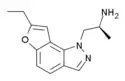

YM-348 | (2S)-1-(7-ethyl-1H-furo[2,3-g]indazol-1-yl)propan-2-amine | 372163-84-3 |

|